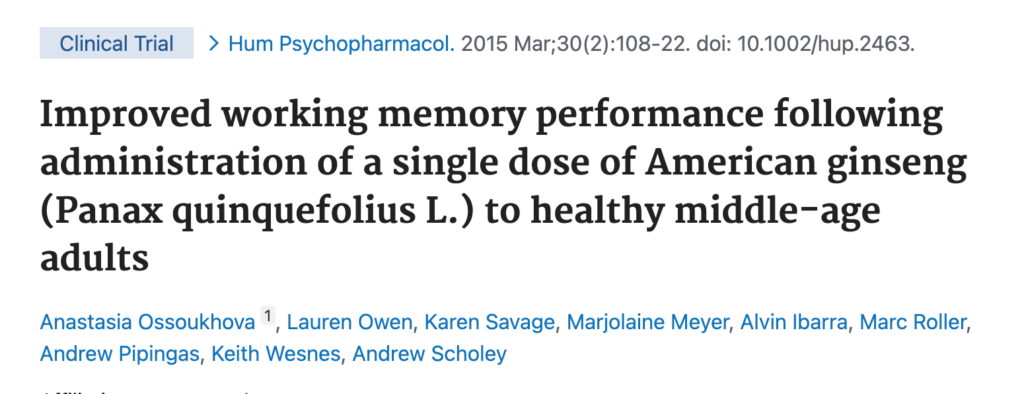

In a clinical trial conducted by Human Psychopharmacology:

The neuroscientists gave an extract of this herb to 40 to 60 years old men and women

And after just 3 hours of taking it…

How well their brains perform or function when it comes to remembering and processing information significantly improved

This is just 3 hours!

How about 3 weeks or 6 weeks?

In another research carried out by Phytotherapy Research, the researchers gave the extract of this herb to 61 adults and after taking it for 2 weeks…

The neuroscientists concluded that the adults showed…

Longer-lasting improvements in working memory

Working memory is important for reasoning and decision making

In a clinical trial by Regulatory Toxicology & Pharmacology, the researchers discovered that an extract called cereboost in this herb improves memory, mental clarity and sharpness within hours of taking it

And it does that by increasing acetylcholine levels